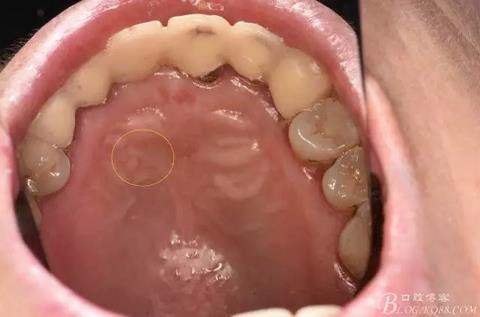

圖4.腭側觀:12根尖正對的腭粘膜隆起、有波動感